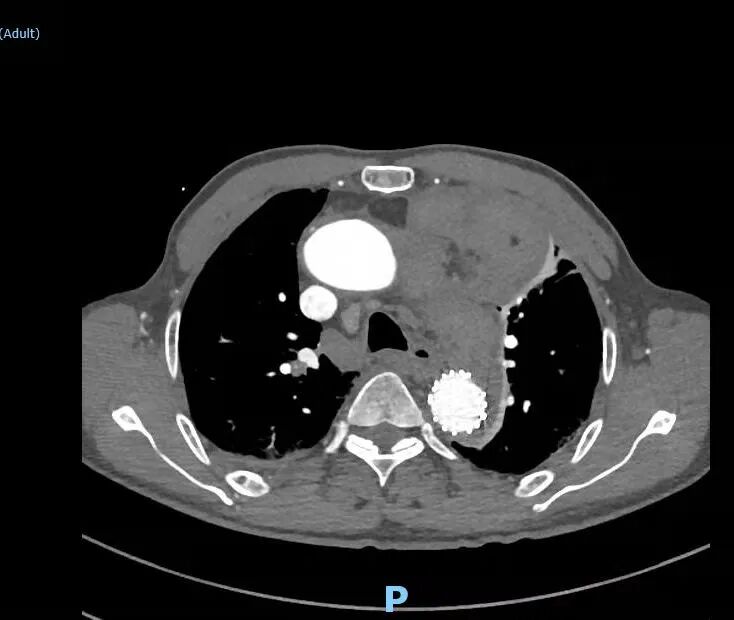

不慎扭腰 疼痛威胁老人生命 据患者的大儿子曹先生介绍,老人今年75岁,家住旺苍县盐河镇,病前一直在家务农。 5月22日晚上20时许,老人洗漱结束后,在院坝里向外泼脏水时,感觉“闪”了一下腰,腰间传来阵阵刺痛。 不一会儿,疼痛加剧,老人有点受不住了。 居家的大媳妇通过电话把情况告诉了在外务工的丈夫曹先生。曹先生认为老人是扭伤了腰,到村卫生室处理一下,拿点止痛药吃就可以了。 大约当天晚上21点多,老人到村卫生室输上了液,结果症状未缓解,痛得汗珠如豆而下。 什么原因导致仅仅是闪了一下腰的老人,突然胸背部产生如此剧烈的疼痛呢? 在没有任何检测硬件条件支撑的村卫生室,病因难以诊断。 在剧烈疼痛持续到第二天早上时,大家提议将其送往县城医院检查。 5月23日上午9时,家人协调到一个亲戚的轿车,将老人送往县城医院。同时,老人在外务工的2个儿子也启程往家乡奔赶。 检查结果显示。主动脉夹层壁间发现血肿,初步诊断为主动脉夹层动脉瘤,考虑患者病情复杂、危重,随时有生命危险,该院医生建议将老人转至广元市第一人民医院就诊治疗。 联合会诊 精准把脉制定大胆“计划” 经过30个小时的辗转,5月24日凌晨2点12分,老人入住广元市第一人民医院,结束了颠簸煎熬。 医院连夜安排了一系列的复查复诊。 然而结果扑朔迷离…… 老人除了疼痛一直没有缓减外,还伴有胸闷、气紧、体表汗流不止等情况,体力受限、但没有明显的活动障碍,没有意识丧失、呕血、黑便、大小便失禁等现象。加上CTA检查主动脉夹层壁间血肿现象明显,综合结果显示,基本和旺苍县县城某医院初诊特征一致。 术前,CTA影像显示,患者左前纵隔巨大占位和左胸腔大面积积液。 但是,问题来了。 老人前纵隔显现大面积阴影,可以确诊为合并前纵隔占位,这一占位是恶性肿瘤还是良性肿瘤,还是其它原因? 前纵隔占位的性质,直接威胁到老人的生命安全,也是治疗方案的关键点。 同时,老人左胸腔伴随着大量积液,积液之多已经把左肺压迫得只有一个成人手拳头大小,这一特征又有点像血管破裂导致。 如果是血管破裂导致,老人因失血过多而发生猝死的风险几率非常高! 那么,胸腔积液到底是什么?它是前纵隔占位诱因还是因血管破裂引起的呢? 5月24日早上,广元市第一人民医院副院长、心胸外科专家何东权在例行巡房时,了解到老人病情的特殊性和复杂性,当即表示:首先确定胸腔积液的成分,来推断老人的病情症结所在。 “看到一针管鲜红的液体,我紧绷的心弦稍稍松了点。”心胸血管外科医师王贤芝通过穿刺取样看到积液颜色,基本断定为血液,而且是鲜血。随后,分析数据也显示积液以血液成分为主体。 即使胸腔积液是血液,也不排除是前纵隔占位引起的出血。 医院又对老人进行主动脉三维重建,显示主动脉弓大弯侧外壁有明显的凸起点,疑似破裂出血灶。 这一结论让老人的主管医生薛春竹忧喜参半:“主动脉夹层破裂导致大量血液漏浸形成胸腔积液的可能性相对较大,反之前纵隔占位引起积液的可能性减少,虽然它对老人的生命依然存在不容忽视的威胁,但相对乐观了不少”。 各类检查结果汇总后,何东权副院长召集心胸血管外科和影像科等相关科室专家进行了联合会诊,大家纷纷发表意见,就疑点进行多角度分析。 讨论的焦点还是集中在前纵隔占位的形成因素以及与胸腔积液的关系。 “前纵隔占位若是恶性肿瘤,那么手术治疗毫无意义。” 老人的病理特征有诸多不合常理的地方,“如果左胸腔内全是血液,为什么患者在大失血前提下,还没有休克?” CT室专家认为,从影像看,前纵隔占位虽然有肿瘤特征,但阴影部分密度分散,而且前纵隔和胸腔之间有清晰的隔离带,不排除因胸腔积血通过膜壁薄弱处渗透到前纵隔而形成占位阴影的可能。 “患者病情恰恰特殊在于,左胸腔积液把左肺压迫收缩到只有拳头大小,也就把左肺中的肺循环体系内约500ml血液挤压进入人体血液大循环中,补充了体供血液量,这或许是目前患者没有休克的主要因素。”心胸血管外科主任医师张文林分析。 “如果前纵隔占位是肿瘤,唯一的办法是开胸手术。高龄、大失血,加上伴有肾功能、前列腺增生等其它病情,老人基本上坚持不到开胸手术结束。”心胸血管外科医师何杨提出自己的担忧。 “老人家的血还在漏失,随时可能发生猝死,十分危急。”何东权副院长提议,根据老人的“突然疼痛、胸腔积血”等病理特点,利用微创技术,只针对出血点进行修复性抢救治疗,目前,保生命是最大的前提。 这一提议得到大家一致认可。 30分钟 上演生命抢夺战 5月26日早上8点,手术开始。 手术施展开来就是和时间赛跑,和死神赛跑。 麻醉之后,从足背动脉穿刺右侧股动脉一路上行,边走边造影,行至升主动脉后,造影显示,主动脉弓大弯侧外壁破口明确,和术前主动脉三维重建显影吻合。 医生沿左锁骨下动脉后缘远端释放支架覆盖主动脉弓大弯侧外壁,覆盖后,造影显示,血管显影良好,未见明显内漏。 短短30分钟,在先进硬件设施设备的帮助下,广元市第一人民医院心胸外科的专家们,凭借精诚团结的团队精神、默契配合和高超技艺,成功堵住了老人体内血液循环体系的“决堤口”,将老人的生命从死亡的边缘上“拉”了回来。 术后,一边输血,一边从老人左胸腔抽出1000ml多的积血。 目前,老人左肺恢复正常,精神面貌、饮食状况得到有效改善,胸背部疼痛消失,身体机能全部转优。 术后,患者左前纵隔占位逐渐减小 左胸腔未见积液 术后,患者主动脉弓大弯侧外壁光滑 未见内漏 术后第三天,患者各项指标转优